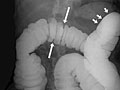

- En un estudio de doble contraste o de contraste con aire, primero se llena el colon de bario y a continuación se drena el bario. Esto deja solo una capa delgada de bario en la pared del colon. El colon entonces se llena con aire. Esto proporciona una visión detallada de la superficie interior del colon. Hace que sea más fácil ver zonas estrechadas (compresiones), divertículos e hinchazón.

El enema de bario, o examen del tubo digestivo inferior, es una radiografía del intestino grueso (colon y recto).